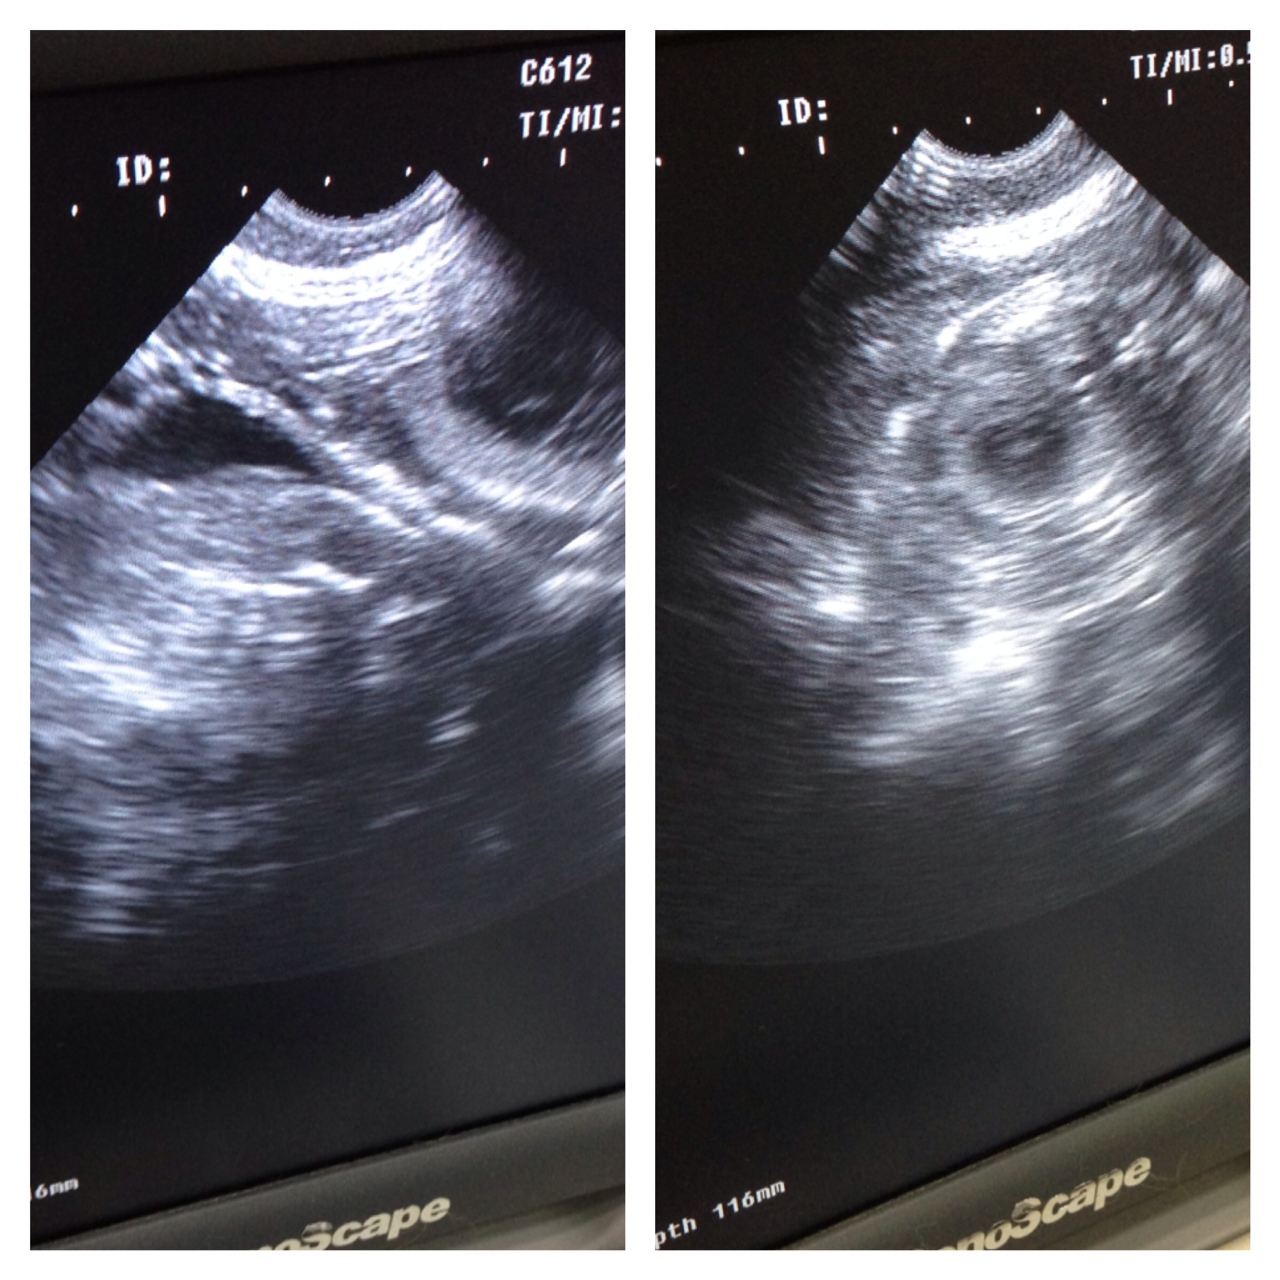

ไปทำอัลตร้าซาวน์ คุณหมอบอกว่าท้องละมากกว่า 6 ครับ